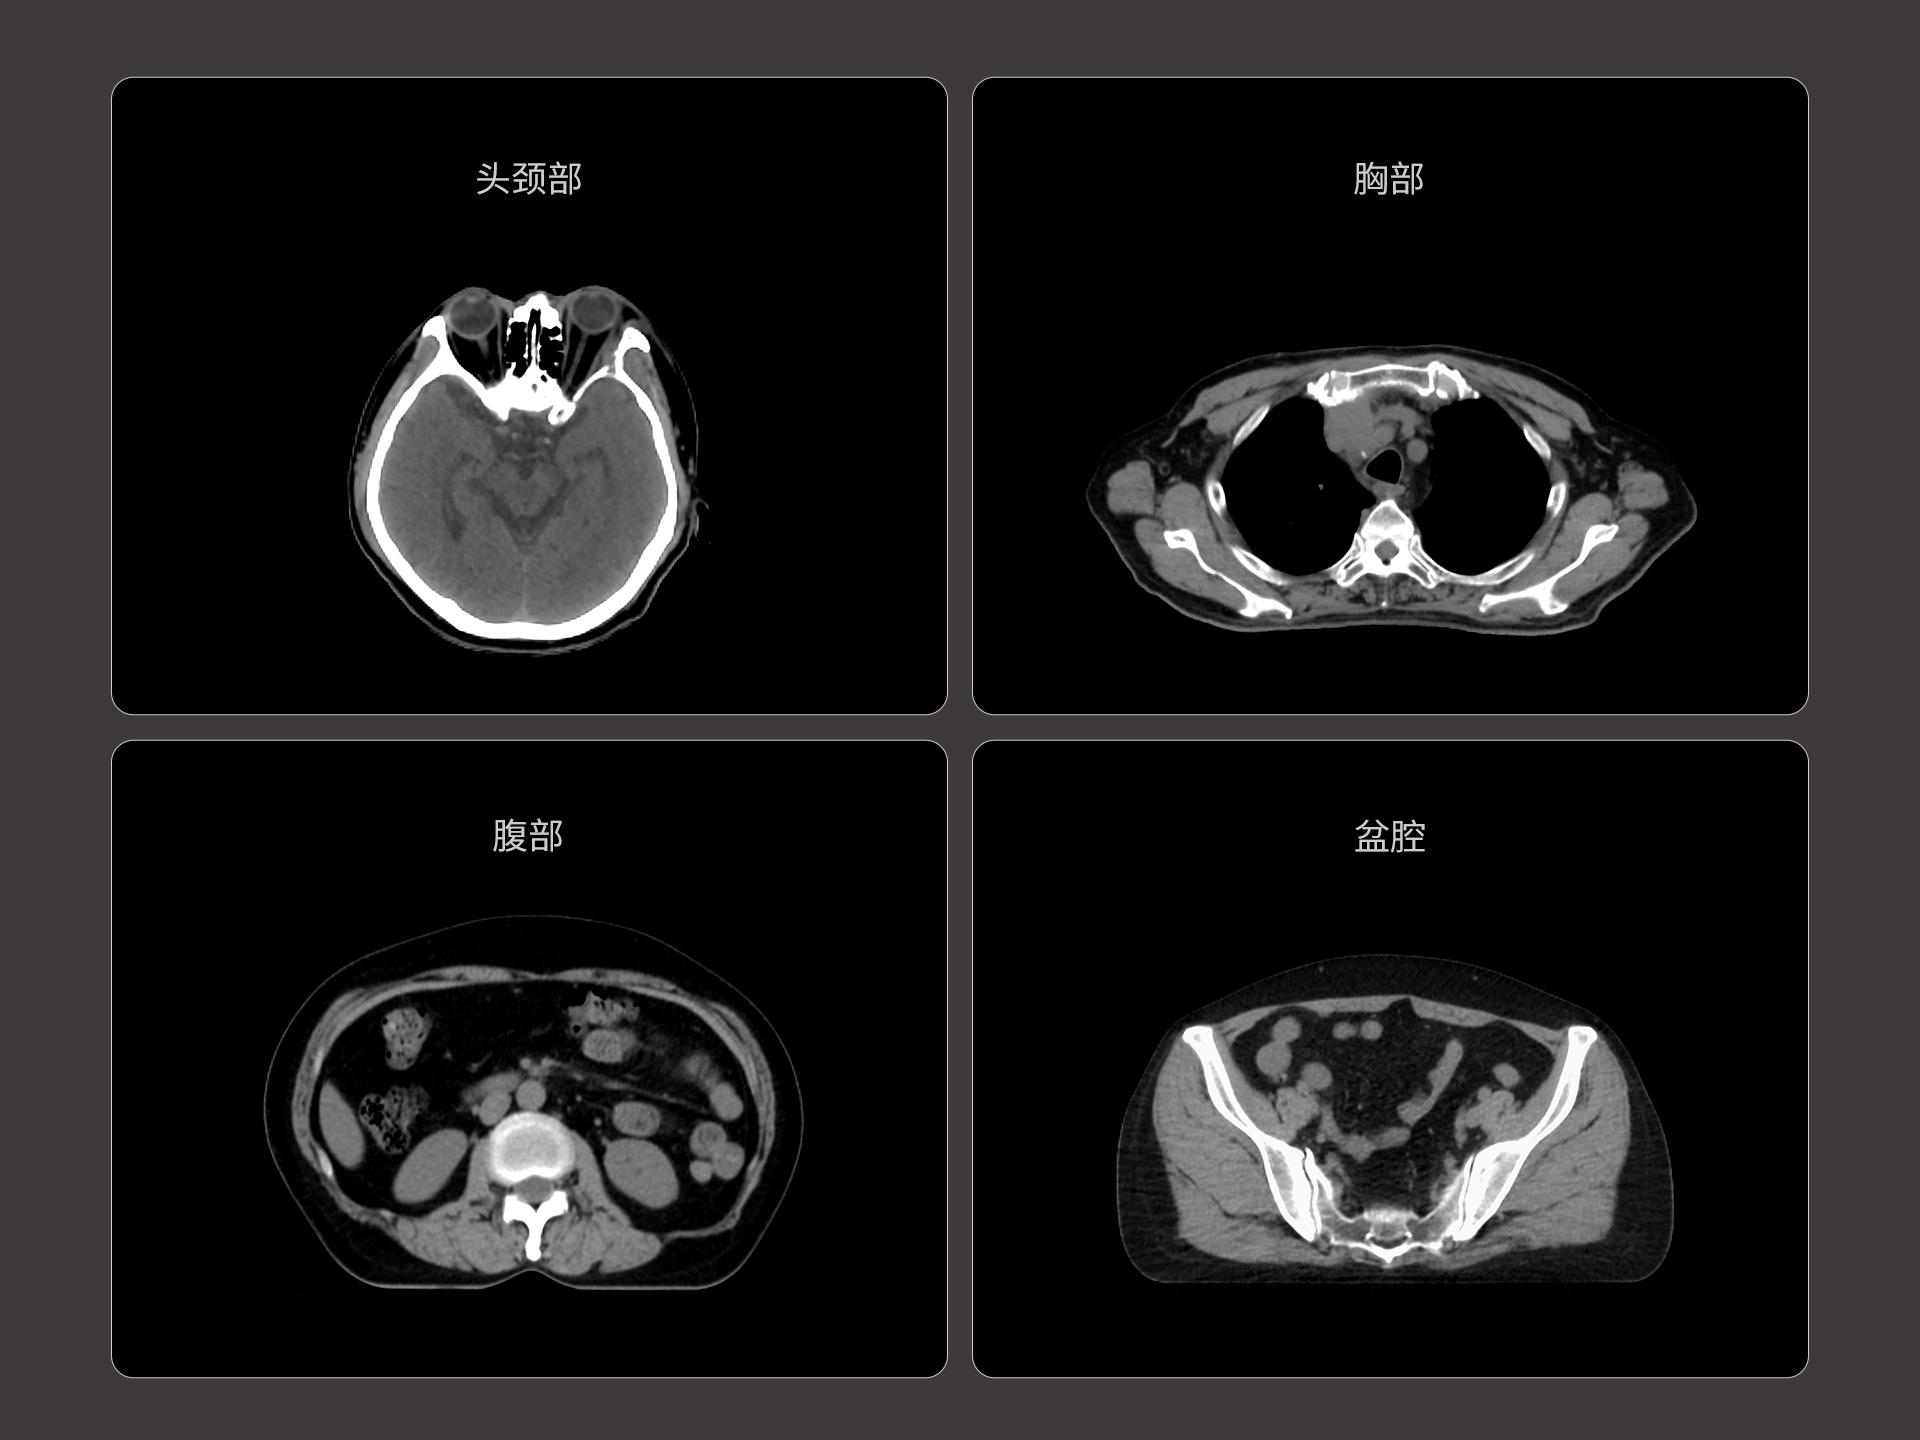

uLinac HalosTx®搭载新一代 87cm 大孔径诊断级CT图像引导系统,全能进阶,实现高清图像质量和全景视野的完美平衡,开辟全疗程 「影像感知」 ,为临床提供更自信、更全面的临床依据。

扇形束成像,极低散射,媲美CT-sim的影像品质

3mm @ 0.3% 高软组织对比度,0.55mm薄层扫描,精确鉴别肿瘤靶区边界

87cm CT影像孔径设计适配多种摆位姿势,兼顾不同体型患者

支持CT、MR、PET多模态影像及全身100+器官勾画模型,准确度高、分割速度快、重现性好,提高临床勾画效率与一致性。